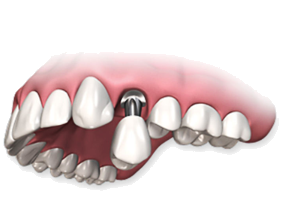

Установка моста на двух имплантатах

Восстановление челюсти на 4-х

или 6-ти имплантатах